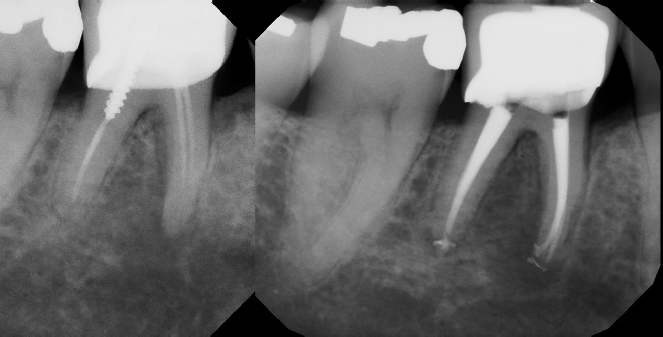

Root Canal Retreatment - Meriden 8 mos. recall Post-op Pre-op